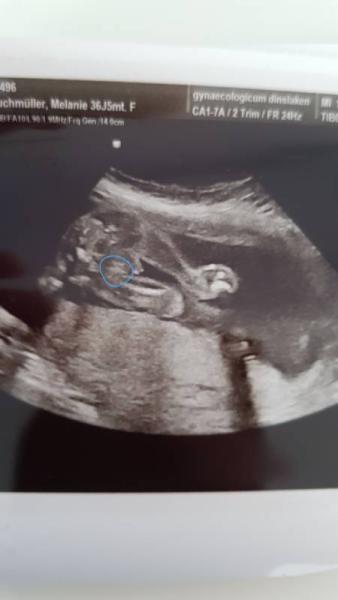

Hallo vlt. könnt ihr helfen Ärzte sind sich nicht sicher erst immer Mädchen dann doch wieder junge bei meinem Sohn sah es anders aus was meint ihr?

Bild zu ultraschall welches geschlecht - Schwanger - wer noch? Rund um die Schwangerschaft

Ich finde es sieht nach einem jungen aus. Erwarte unser 2tes Kind. Diesmal ein Mädchen, das sieht ganz anders aus als bei meinem Sohn.

Nicht das, sondern rechts davon. Junge.

Normalerweise sagt man ja, wenn diese "Kaffeebohne" mit den 3 Strichen zu sehen ist, das es ein Mädchen ist. Die ist zu sehen, aber nicht mittig. Das ist meine Laienmeinung. Ich wünsche auf jeden Fall alles Gute !

Für mich auch ein Junge

Ich würde auch auf junge tippen

ich werde mich dann wohl damit abfinden müssen das es wieder ein junge wird ich habe mich so gefreut als es erst immer Mädchen hieß habe auch von einem mädchen geträumt die Mädels Kleidung bin ich grade schon am verkaufen